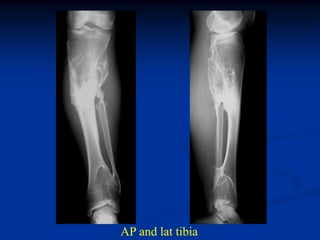

Case #625.1                 Multiple hereditary exostoses

50 yr old female with short stature and R hip pain for years

AP and lateral of right hip

AP and lat tibia

Proximal humeral x-rays